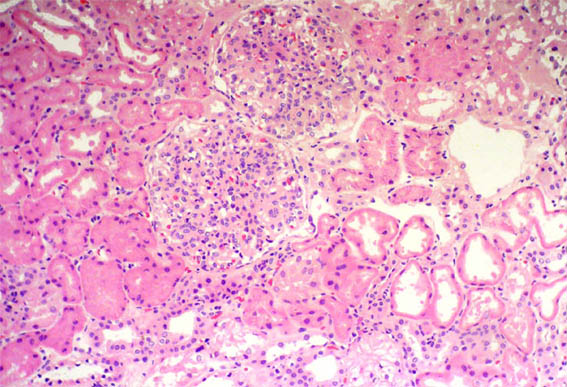

Observe las imágenes de la biopsia

renal.

Figura 1.

H&E, X100.